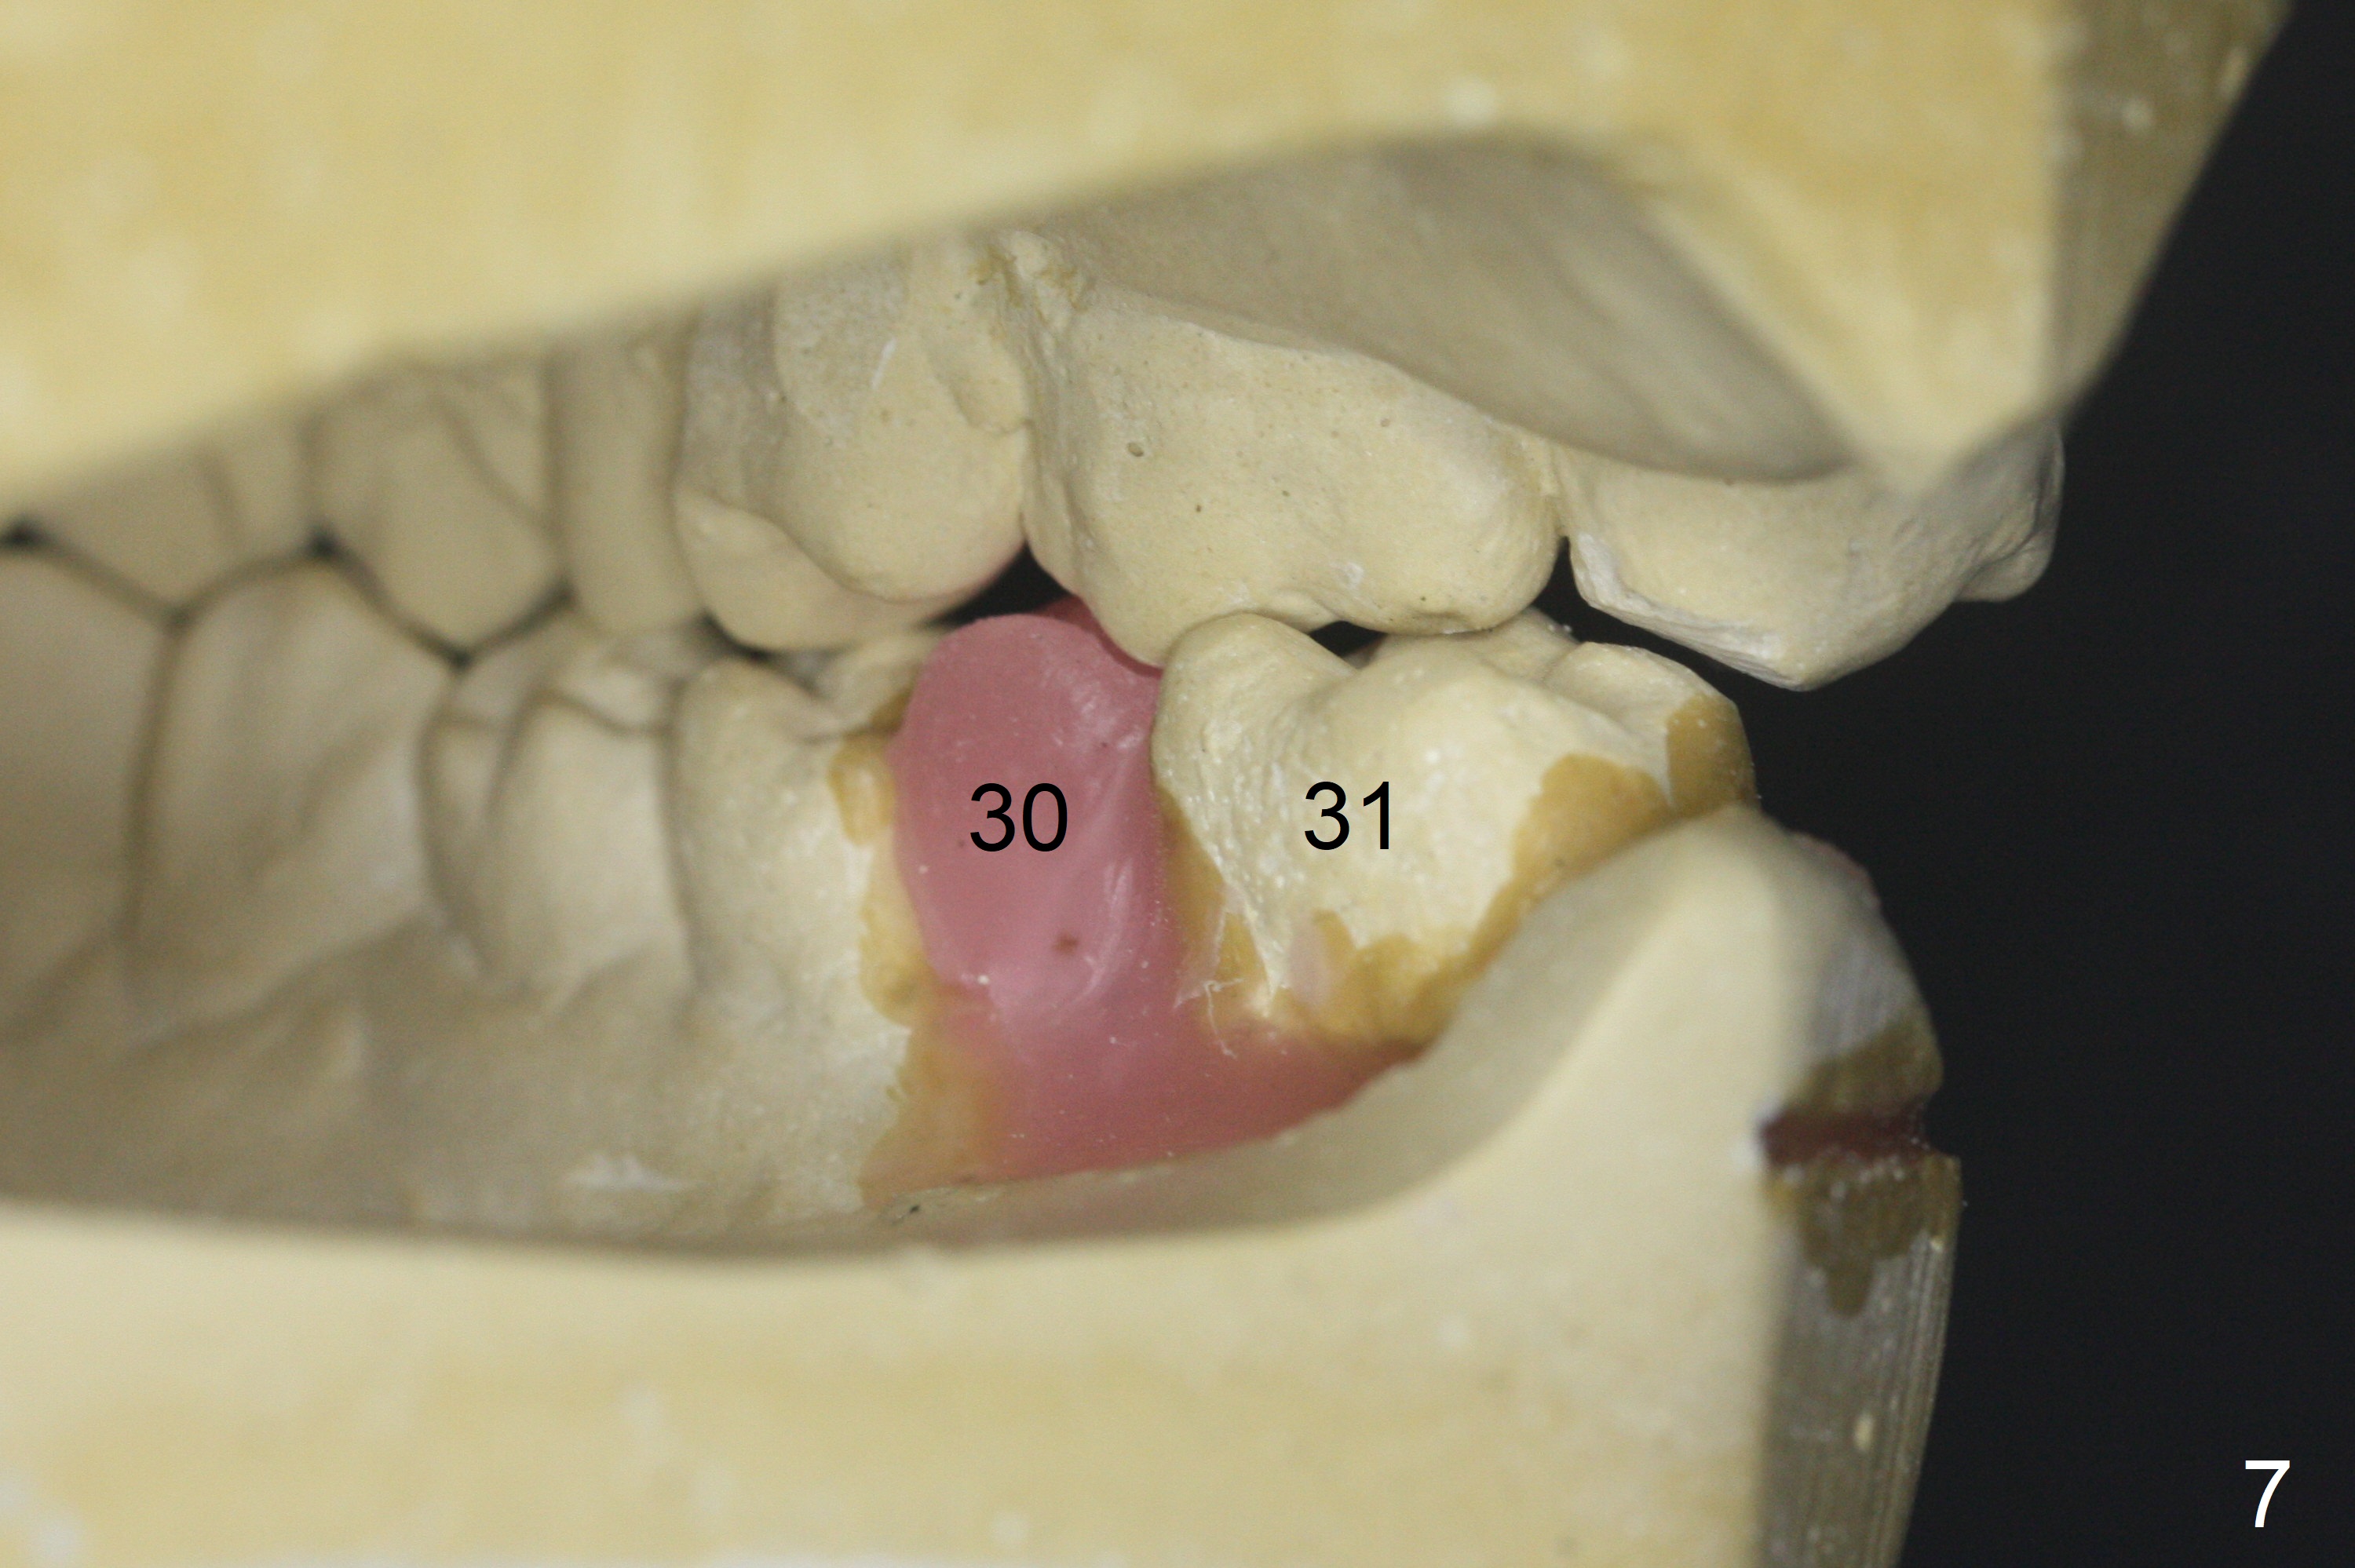

A 64-year-old man has discomfort with the lower left bridge and a loose tooth on the left (Fig.1). It appears that 4 implants are to be placed at #18,19,30 and 31. Since the tooth #4 and 13 are palatalized (Fig.2-4), the teeth #2 and 3 are mesialized (Fig.2 arrow). Besides, the ridge at #30 must be atrophic due to long termed edentulism. A small-diameter implant will be placed at #30 with premolar width (Fig.6-13), while the implant at #31 will be placed distal (arrow, as compared to Fig.2). To establish harmonious occlusion at provisional and final stages, the palatal slope of the mesiopalatal cusp of the tooth #2 will be adjusted (Fig.10).